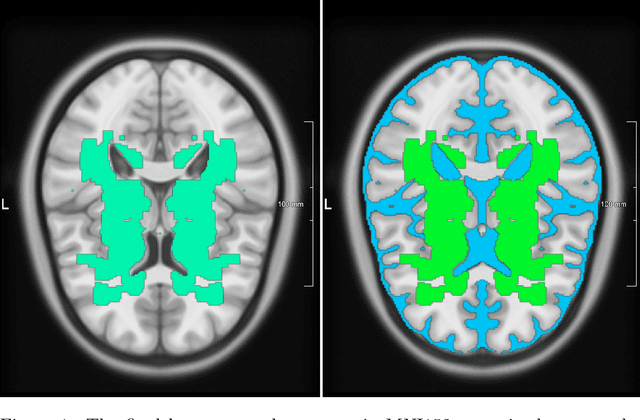

Abstract:Imaging markers of cerebral small vessel disease provide valuable information on brain health, but their manual assessment is time-consuming and hampered by substantial intra- and interrater variability. Automated rating may benefit biomedical research, as well as clinical assessment, but diagnostic reliability of existing algorithms is unknown. Here, we present the results of the \textit{VAscular Lesions DetectiOn and Segmentation} (\textit{Where is VALDO?}) challenge that was run as a satellite event at the international conference on Medical Image Computing and Computer Aided Intervention (MICCAI) 2021. This challenge aimed to promote the development of methods for automated detection and segmentation of small and sparse imaging markers of cerebral small vessel disease, namely enlarged perivascular spaces (EPVS) (Task 1), cerebral microbleeds (Task 2) and lacunes of presumed vascular origin (Task 3) while leveraging weak and noisy labels. Overall, 12 teams participated in the challenge proposing solutions for one or more tasks (4 for Task 1 - EPVS, 9 for Task 2 - Microbleeds and 6 for Task 3 - Lacunes). Multi-cohort data was used in both training and evaluation. Results showed a large variability in performance both across teams and across tasks, with promising results notably for Task 1 - EPVS and Task 2 - Microbleeds and not practically useful results yet for Task 3 - Lacunes. It also highlighted the performance inconsistency across cases that may deter use at an individual level, while still proving useful at a population level.

Abstract:Lacunes of presumed vascular origin are fluid-filled cavities of between 3 - 15 mm in diameter, visible on T1 and FLAIR brain MRI. Quantification of lacunes relies on manual annotation or semi-automatic / interactive approaches; and almost no automatic methods exist for this task. In this work, we present a two-stage approach to segment lacunes of presumed vascular origin: (1) detection with Mask R-CNN followed by (2) segmentation with a U-Net CNN. Data originates from Task 3 of the "Where is VALDO?" challenge and consists of 40 training subjects. We report the mean DICE on the training set of 0.83 and on the validation set of 0.84. Source code is available at: https://github.com/hjkuijf/MixLacune . The docker container hjkuijf/mixlacune can be pulled from https://hub.docker.com/r/hjkuijf/mixlacune .

Abstract:Cerebral microbleeds are small, dark, round lesions that can be visualised on T2*-weighted MRI or other sequences sensitive to susceptibility effects. In this work, we propose a multi-stage approach to both microbleed detection and segmentation. First, possible microbleed locations are detected with a Mask R-CNN technique. Second, at each possible microbleed location, a simple U-Net performs the final segmentation. This work used the 72 subjects as training data provided by the "Where is VALDO?" challenge of MICCAI 2021.